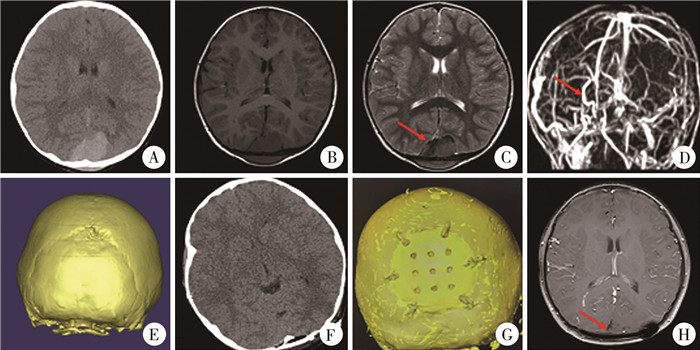

图 1 1例朗格罕细胞组织细胞增生症患儿的影像学资料 Fig.1 Imaging data of a child with LCH 注 A:术前颅脑CT轴位脑窗;B:术前颅脑CT轴位骨窗;C:颅脑MRI轴位T2;D:颅脑MRI轴位T1;E:术前颅脑CT骨窗三维重建;F:术后颅脑CT轴位脑窗;G:术后颅脑CT轴位骨窗;H:随访时颅脑CT骨窗三维重建 |

图 2 1例淋巴瘤患儿的影像学资料 Fig.2 Imaging data of a child with lymphoma 注 A:术前颅脑CT轴位脑窗;B:颅脑MRI轴位T1;C:颅脑MRI轴位T2,红色箭头提示上矢状窦受压移位;D:术前颅脑MRV,红色箭头提示上矢状窦受压移位;E:术前颅脑CT骨窗三维重建;F:术后颅脑CT轴位脑窗;G:随访时颅脑CT骨窗三维重建;H:随访时颅脑增强MRI轴位T1,红色箭头提示上矢状窦复位,局部无肿瘤复发 |